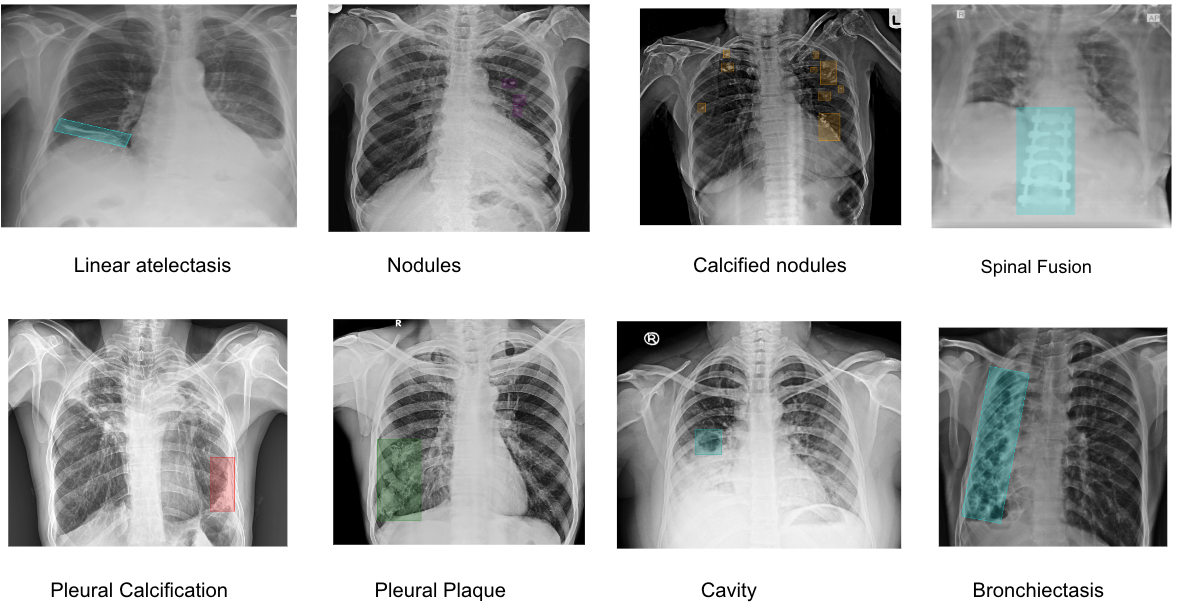

This paper presents an AI-based approach designed to address these challenges in the Indian healthcare system by enhancing CXR pathology detection capabilities. The system is capable of detecting 75 distinct pathologies, from common infections to complex thoracic conditions, using a combination of Vision Transformers for classification, Faster R-CNN for detection, and UNet for segmentation [5]. This multi-layered approach enables precise identification of abnormalities while automating the detection and reporting process. We begin by outlining the challenges in CXR reporting within India and describe how AI is uniquely positioned to tackle these issues [6]. The paper also elaborates on the methodology, covering the system architecture and workflow from input to pathology detection, aimed at providing accurate and actionable insights [7].

The AI system developed for this study is a computer-aided detection (CAD) tool designed for the identification and differentiation of various radiological abnormalities present in chest X-rays (CXRs). This system incorporates multiple deep-learning algorithms, each tailored to detect specific pathologies, covering a comprehensive range of thoracic conditions(Ronneberger et al., 2015). The models were trained on a large-scale dataset consisting of over 5 million CXR images, with expert radiologist annotations used for supervised learning(Firdiantika & Jusman, 2022). The AI system aims to detect abnormalities such as lung nodules, pleural effusion, pneumothorax, cardiomegaly, consolidation, fibrosis, hilar enlargement, rib fractures, etc.

Moving beyond classification, the detection capability of the model was evaluated using Precision, Recall, and Intersection over Union(IoU) metrics. Precision indicates how many of the abnormalities identified by the model were true positives, while recall measures the ability of the model to identify all existing abnormalities in the chest X-rays. IoU was utilized to evaluate the overlap between predicted regions of interest and the actual ground truth, offering a quantitative assessment of the model’s localization accuracy. Performance metrics for all 75 detected pathologies were documented, providing an in-depth view of how well the system performed for each specific condition. The metrics for precision, recall for each of these pathologies are presented in the table below, showcasing the AI’s proficiency in both identifying and accurately localizing abnormalities. These results highlight the system’s ability to support clinical workflows, enhancing both the accuracy and speed of radiology reporting.